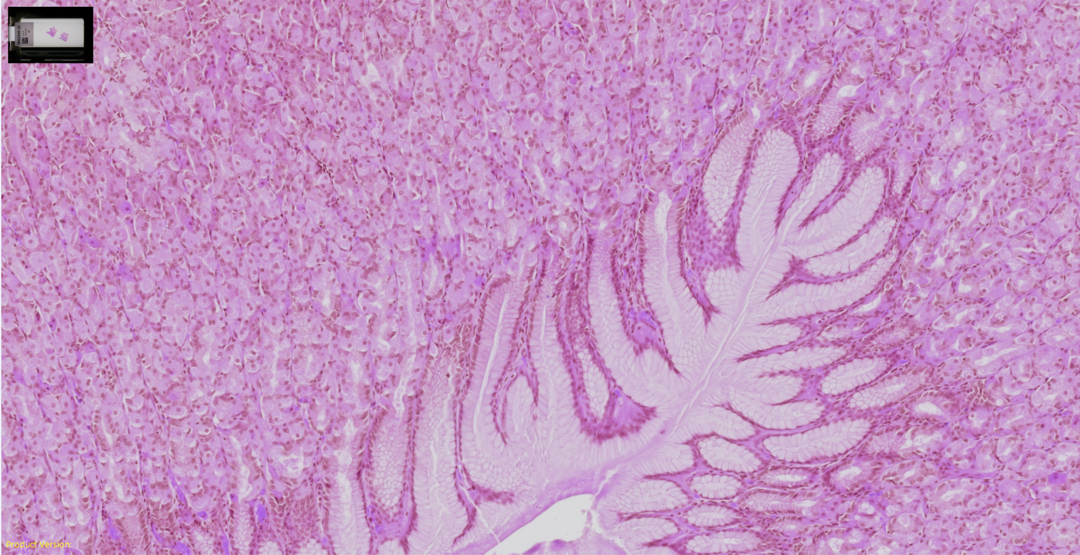

您多年來一直信賴的光學(xué)品質(zhì)如今已體現(xiàn)在專用玻片掃描系統(tǒng)中。基于病理學(xué)成像領(lǐng)域深厚的專業(yè)知識(shí)而打造,為組織學(xué)和細(xì)胞學(xué)樣品提供顯微鏡質(zhì)量的圖像。可驗(yàn)證的數(shù)字成像流程,系統(tǒng)化的色彩再現(xiàn)評(píng)估方法讓真實(shí)顏色準(zhǔn)確再現(xiàn)。

清晰捕捉各種組織和染色的細(xì)節(jié)

胃組織,H&E(蘇木素和伊紅)染色